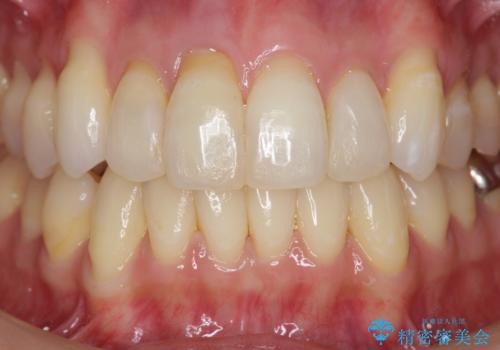

上顎4前歯は、根管治療の既往があり、虫歯も見られたことからブリッジによる治療で審美性の回復を行うとともに臨在歯の虫歯もセラミック治療を行っていきます。

- 44万円(仮歯・ジルコニアクラウン×4)費用は治療当時の料金となります

欠損部の歯ぐきの量が足りない場合は、移植を行い歯肉を増大させることもありますが、今回は仮歯で様子を見た結清掃性・審美性に問題が出なかったので行いませんでした。